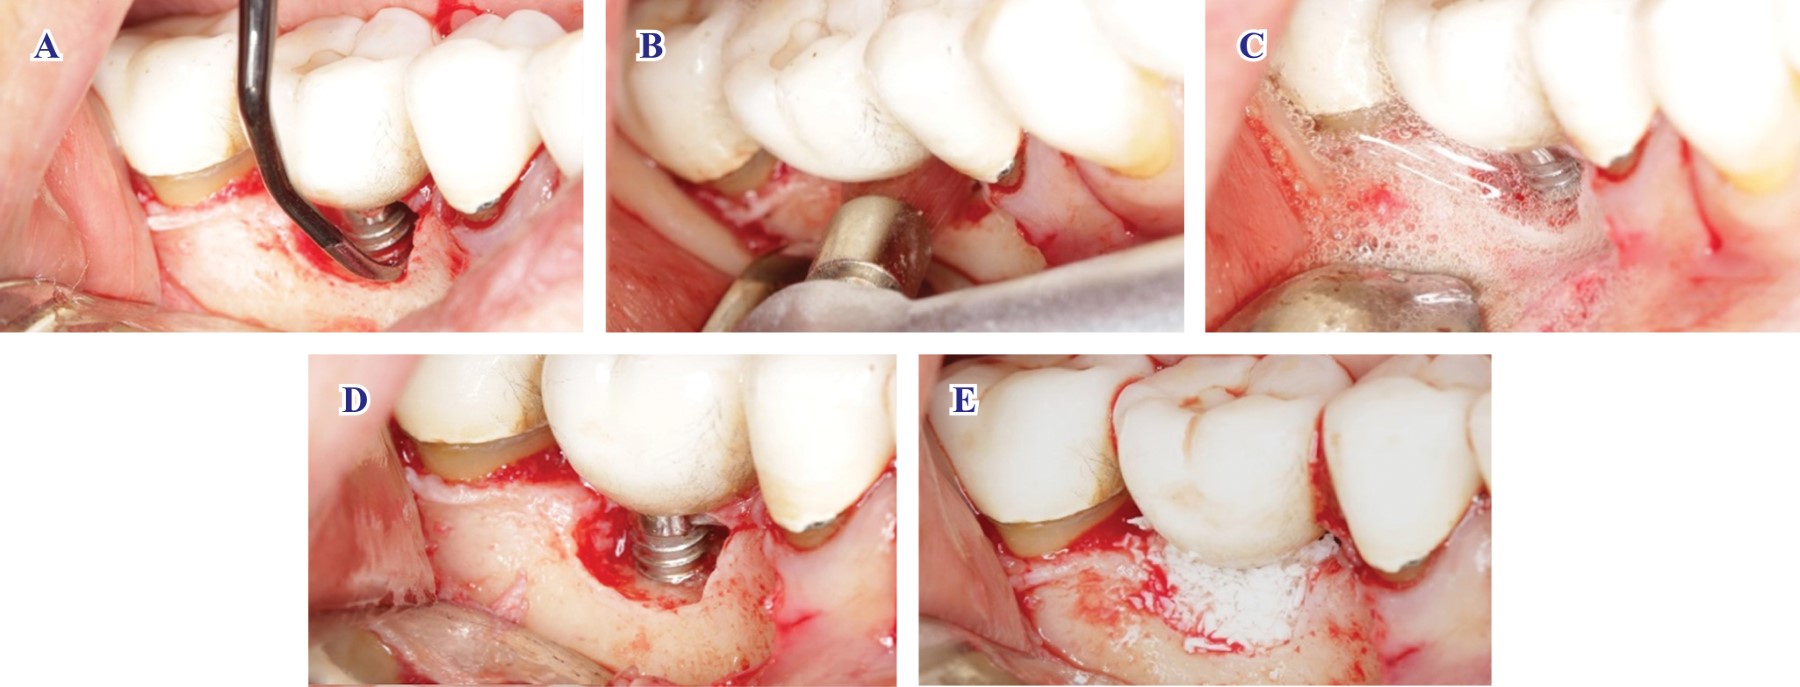

Resultados. La curación transcurrió sin incidentes, sin evidencia de infección o retraso en la cicatrización y la paciente reportó un dolor mínimo. A las 20 semanas se evaluaron los resultados de la terapia periimplantaria, obteniendo profundidades al sondeo de 3, 2 y 3 mm por lingual y 3, 1, 3 mm por bucal, con ausencia de sangrado al sondeo en todos los sitios y un llenado radiográfico de aproximadamente 90% (Figura 3); obteniéndose así los criterios de éxito establecidos por la Federación Europea de Periodontología para el tratamiento de la periimplantitis.12 Si bien no se detectó recesión del tejido blando, sí se pudo observar un ligero achatamiento de las papilas interdentales después de la intervención.

La paciente se expresa satisfecha con los resultados y ya no reporta dolor al cepillado o sangrado de sus implantes.